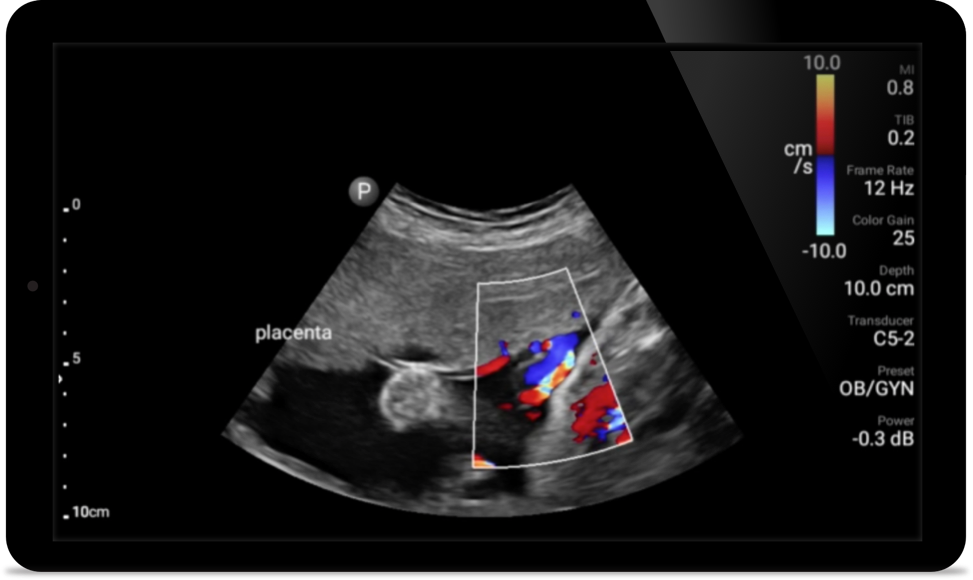

Lumify S4-1 broadband phased array transducer

• 4 to 1 MHz extended operating frequency range

• 2D, color Doppler, M-mode, advanced XRES and multivariate harmonic imaging

• High-resolution imaging for abdominal and cardiac applications: Cardiac, OB/GYN, Lung, Abdomen and FAST imaging preset optimizations Lumify aids life-saving technology in prehospital setting

Get the full picture with clear whole-body imagery for a fast, accurate response during an emergency.